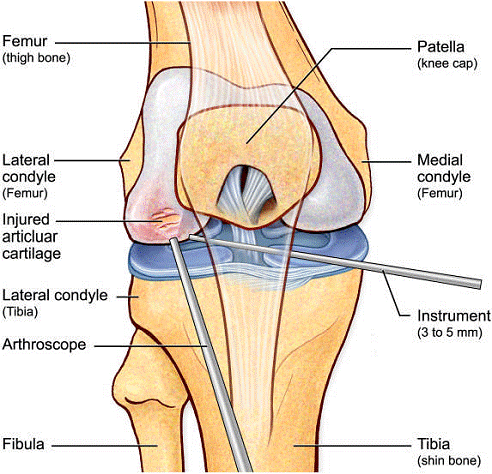

Artroscopia este o investigatie

invaziva care permite vizualizarea foarte buna a spatiului articular cu

ajutorulul artroscopului. Artroscopul este format dintr-un endoscop cu fibra optica, instrument care se introduce direct

in articulatie printr-o mica incizie subcutanata. Artroscopia ofera medicului posibilitatea

de a inspecta suprafetele articulare si tesutul moale din jur: ligamentele si cartilajele.

Introducerea instrumentelor endoscopice permite nu numai examinarea in scop

diagnostic a interiorului articulatiei, dar si tratarea leziunilor articulare

sau indepartarea corpilor straini liberi din spatiul articular, fara a

traumatiza sever tesuturile invecinate, cat si urmarirea evolutiei unei

afectiuni articulare sau monitorizarea eficientei tratamentului.

Un diagnostic de rutina de artroscopie este utilizat pentru a evolua toate compartimentele intra-articulare ale genunchiului. Inainte de efectuarea microfracturii, se raporteaza orice patologie intra-articulara asociata (cum ar fi de menisc).